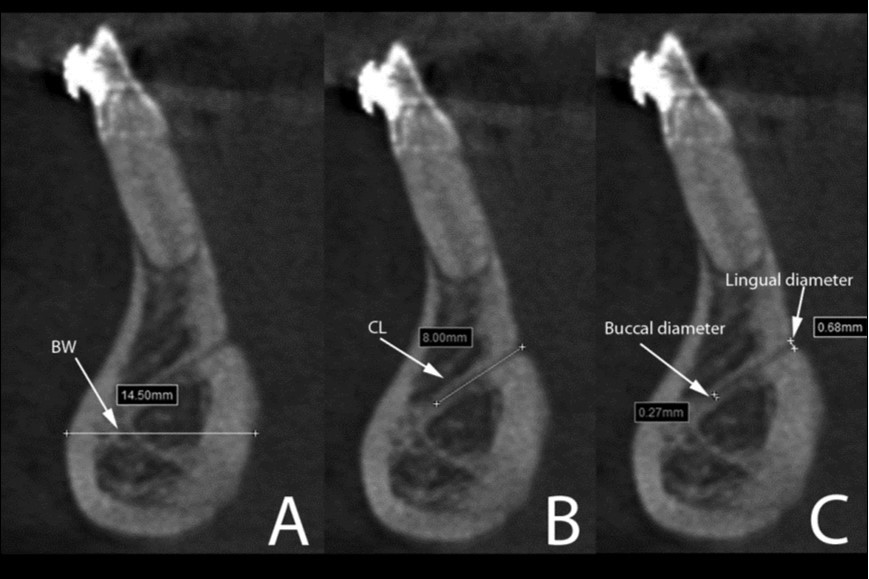

Human, Chimpanzee and Gorilla groups showed significant differences in the dimensions of the mandibular canal, mental foramen, incisive canal, lingual canal and in the anterior mandibular bone width (Figure 4). The Gorilla group showed significant higher medians for the mandibular canal, lingual canal length and bone width than Human and Chimpanzee groups (Table 1).

Figure 4.Cross-sectional views show the lingual canal. Images (A), (B) and (C) show the measurement of bone width (BW, the longest distance in the anterior mandibles under the lingual canal), canal length (CL) and lingual canal diameter (buccal and lingual), respectively.

On the other hand, human mandibles showed significant larger range of mental foramen (3.3mm/2.7-4.0mm) compared to Chimpanzee (2.1mm/1.7-2.7mm) and Gorilla (2.1mm/1.9-2.9mm). No incisive canal could be observed in the Gorilla group, while very few were presented in Chimpanzee. The incisive canal diameter was significantly larger in Human (IC/start: 1.9mm/1.6-2.6mm) than in Chimpanzee (IC/start: 0.9mm/0.8-1.1mm). For the root lengths, the longest third molar was observed in the Gorilla group (13mm/10.1-14.8mm), whereas the Human group presented the longest second premolar (14.5mm/13.4-16.4mm) and Chimpanzee showed the longest canine (18.1mm/15.4-21.9mm).